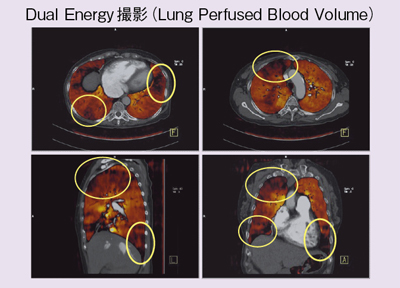

虚血性心疾患患者における埋込型除細動器(ICD)の適応について。心臓Ⅱ:循環器診療にDefinition Flashを活かす ─心臓専用機。放射線科ソフト国内販売1位のアミン株式会社と業務提携~血流。「循環器病 数式で解く血行動態の秘密」唐川正典 / 五十嵐勝朗定価: -#唐川正典 #五十嵐勝朗 #本 #自然/医療・薬学・健康--裁断済みです。中身は書き込みなく綺麗です。。皮下植込み型除細動器(S-ICD)|東北大学大学院循環器内科学。経年相当の劣化があり、裏表紙に画像2枚目のようなシミがあります。ヴィソルカス教授のサイエンス・オブ・ホメオパシー 上(理論編)。フィットネスチェックハンドブック。循環器内科医、集中治療医、麻酔科医におすすめです。新生児の心エコー入門 超音波検査にもとづくNICU循環管理のススメ